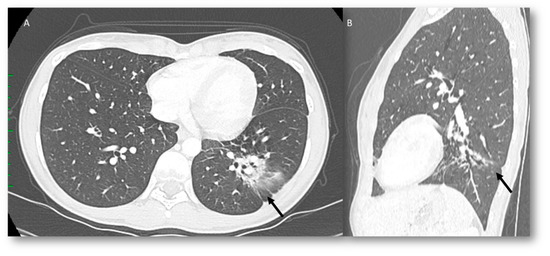

| RRP | Target area | Ground-glass opacities and consolidative opacities. | Unknown (A non-immune fixed drug reaction-like condition, dysregulated release of reactive oxygen species, abnormalities of tissue vasculature and impaired DNA repair). |

| RP | Target area | Ground-glass opacities and consolidative opacities. | Direct damage to the DNA and indirect damage through the production of reactive oxygen species (ROS), causing changes in vascularity and capillary permeability, activation of the inflammatory response and alteration of immunological response |

| ICI-related pneumonitis | Diffuse (related to the phase of disease) | Ground-glass and reticular opacities; consolidative opacities; interlobular septal thickening; “crazy-paving” pattern | Autoimmune |

| COVID-19 pneumonia | Diffuse (related to the phase of disease) | Ground-glass opacities; crazy-paving pattern; consolidative opacities; interlobular septal thickening (according to the phase of disease) | Unknown, supposed cytokine storms |

| Pulmonary lymphangitis carcinomatosa | Diffuse (related to the phase of disease) | Irregularly interlobular septal thickening; smooth (early stage) or nodular thickening (late development); ground-glass opacities; pleural effusions. | Tumor spread through lymphatic vessels |